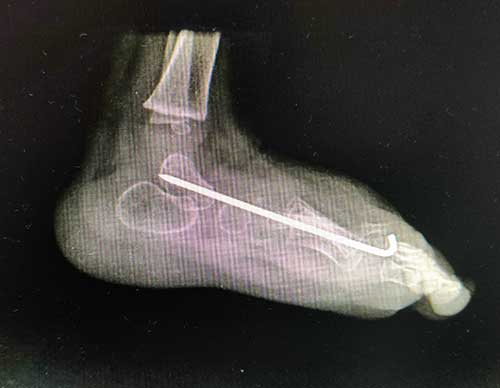

After surgery

The goal of surgery is to correct the position of the bones within the foot. This will likely require lengthening tendons or ligaments to allow the bones to be moved. The bones are then held in place with pins and a cast. The pins can usually be removed in the office in 4 to 6 weeks. A special shoe or brace may be recommended to try to prevent recurrence of the deformity. Your doctor will likely recommend follow up visits for a few years to see make sure the foot grows well and doesn’t need additional treatment.